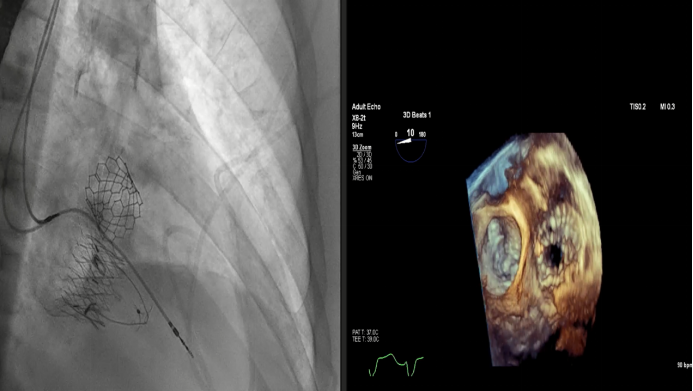

Dee Dee Wang教授分享了Henry Ford Hospital前4例Lux-Valve Plus的植入經驗,并提示術中確定瓣葉夾持鍵的位置處于三尖瓣瓣環下方(右心室側),以及室間隔固定片與室間隔的相對位置關系是最關鍵的兩個步驟。使用經胃底短軸切面,有時配合右室流入/流出道切面的X-plane就能較容易地獲取相關影像。由于Lux-Valve Plus對超聲影像的要求較低,手術過程會相對比較流暢。